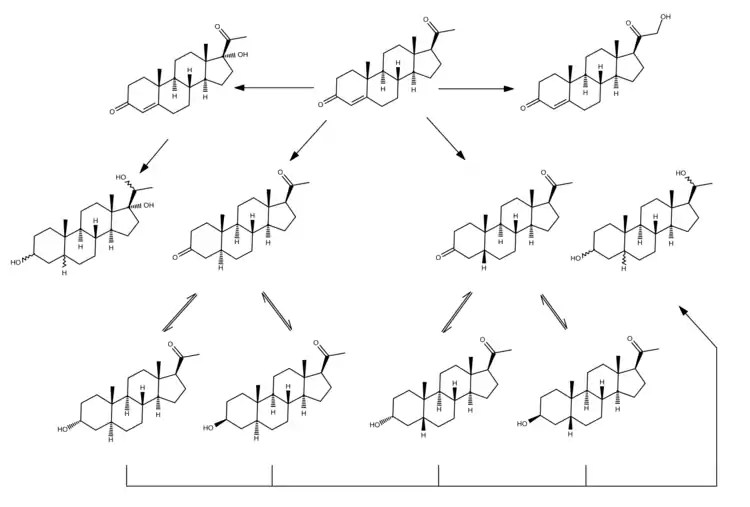

In mammals, progesterone, like all other steroid hormones, is synthesized from pregnenolone, which itself is derived from cholesterol.

Cholesterol undergoes double oxidation to produce 22R-hydroxycholesterol and then 20α,22R-dihydroxycholesterol. This vicinal diol is then further oxidized with loss of the side chain starting at position C22 to produce pregnenolone. This reaction is catalyzed by cytochrome P450scc.

The conversion of pregnenolone to progesterone takes place in two steps. First, the 3β-hydroxyl group is oxidized to a keto group and second, the double bond is moved to C4, from C5 through a keto/enol tautomerization reaction.[108] This reaction is catalyzed by 3β-hydroxysteroid dehydrogenase/δ5-4-isomerase.

Progesterone in turn is the precursor of the mineralocorticoid aldosterone, and after conversion to 17α-hydroxyprogesterone, of cortisol and androstenedione. Androstenedione can be converted to testosterone, estrone, and estradiol, highlighting the critical role of progesterone in testosterone synthesis.

Metabolism of progesterone in humans[129]